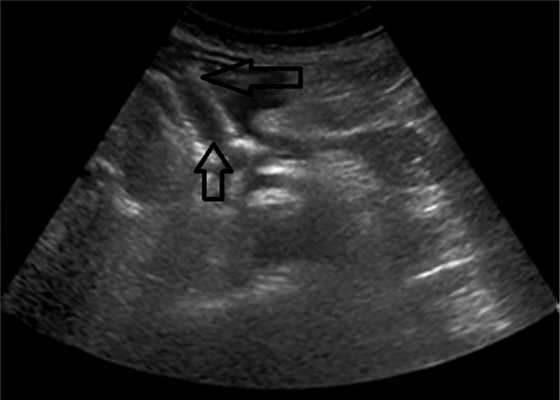

ПК локализовались в теле ПЖ у 7 (30,4%) пациентов, в хвосте ПЖ — у 7 (30,4%), в головке ПЖ — у 6 (26,2%) (рис. 1). Рис. 1. Псевдокиста головки поджелудочной железы (изображение при ультразвуковом исследовании). Стрелками указаны полость псевдокисты (1), бессосудистая зона (2). The arrows indicate pseudocyst cavity (1), avascular zone (2). У 3 (1%) больных имело место сочетанное расположение ПК в головке и теле ПЖ.

Контрольное УЗИ, выполненное перед выпиской, выявило отсутствие жидкостного образования у 18 (81,9%) пациентов, у 4 (18,2%) — уменьшение полости ПК более чем в 2 раза (рис. 3). Рис. 3. Стент в области головки поджелудочной железы, полость отсутствует, стрелками указаны края стента (изображение при ультразвуковом исследовании).